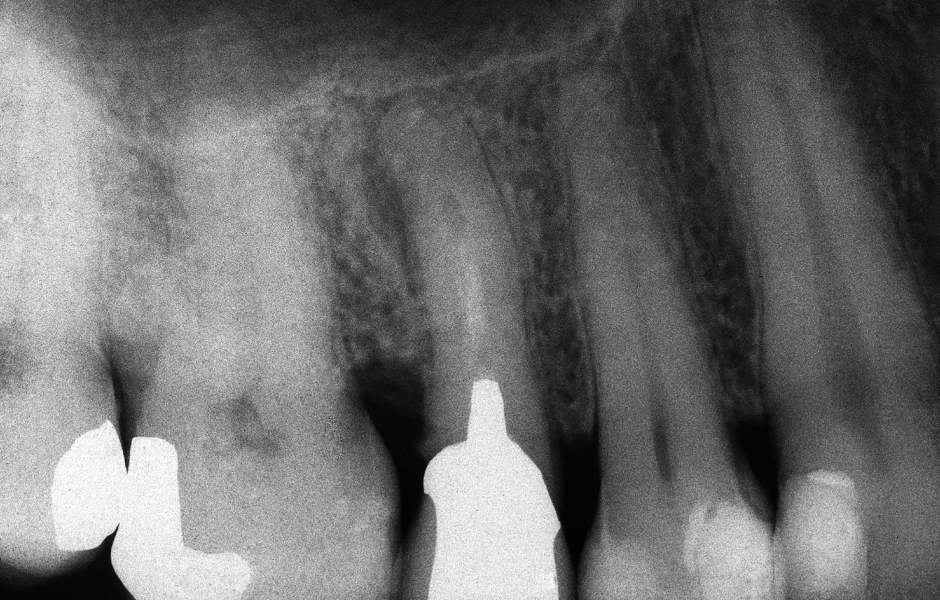

Obr. 2.1: Předoperační rentgenový snímek horního pravého druhého moláru. Je patrná drobná laterální radiolucence indikující přítomnost laterálního kanálku.

Obr. 4.1: Předoperační snímek horního levého prvního moláru. Oba kanálky mesiobukálního kořene byly kompletně kalcifikované a nebylo možné je ortográdně zprůchodnit.